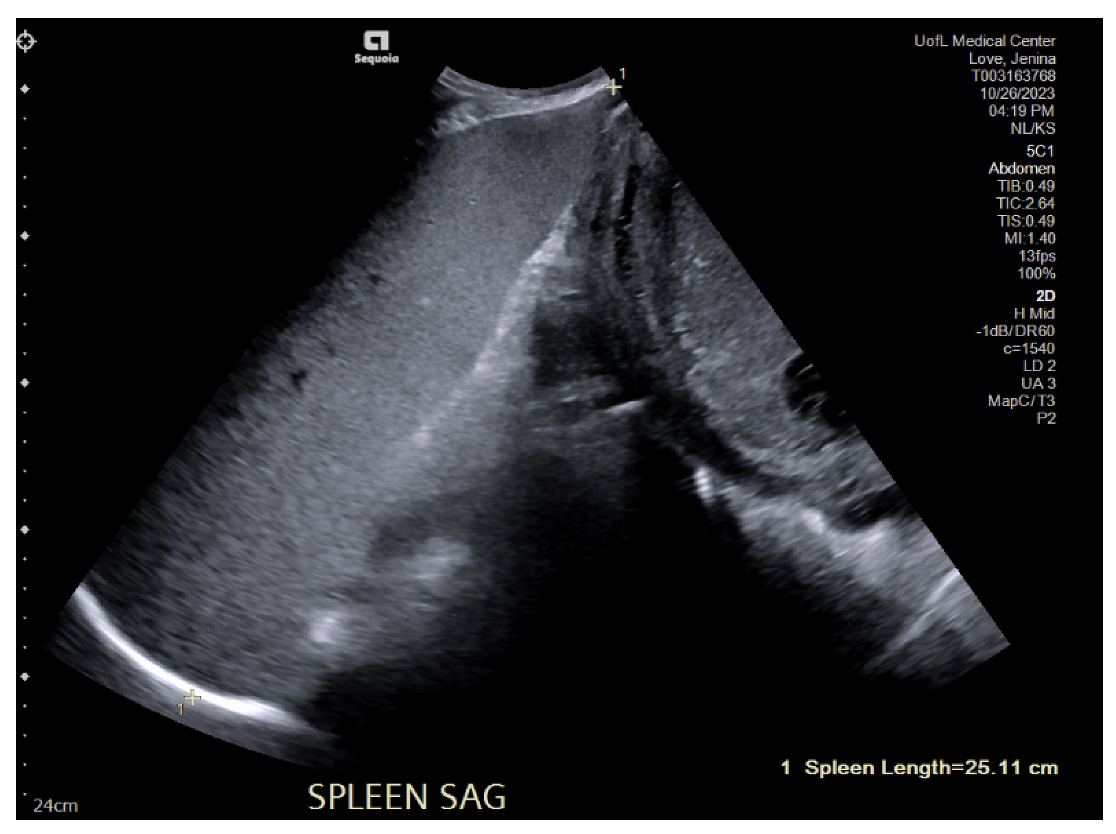

This patient returned to care one month and twenty days later with complaints of constant left-sided abdominal pain. The hematology/oncology, infectious disease, and general surgery teams were consulted. The specific workup performed by Infectious Disease during both admissions can be referenced below in Table 2. The hematology/oncology team was concerned about her massive splenomegaly, now 25 centimeters as demonstrated in Figures 1A and 1B, and the potential for spontaneous rupture. This admission, hematology/oncology completed additional workup with Next Generation Sequencing (NGS) panel, BCR-ABL mutation, JAK exon 12, 13. These returned as negative, and our multidisciplinary team concluded that the cause of splenomegaly could be determined from surgical resection and pathology analysis.